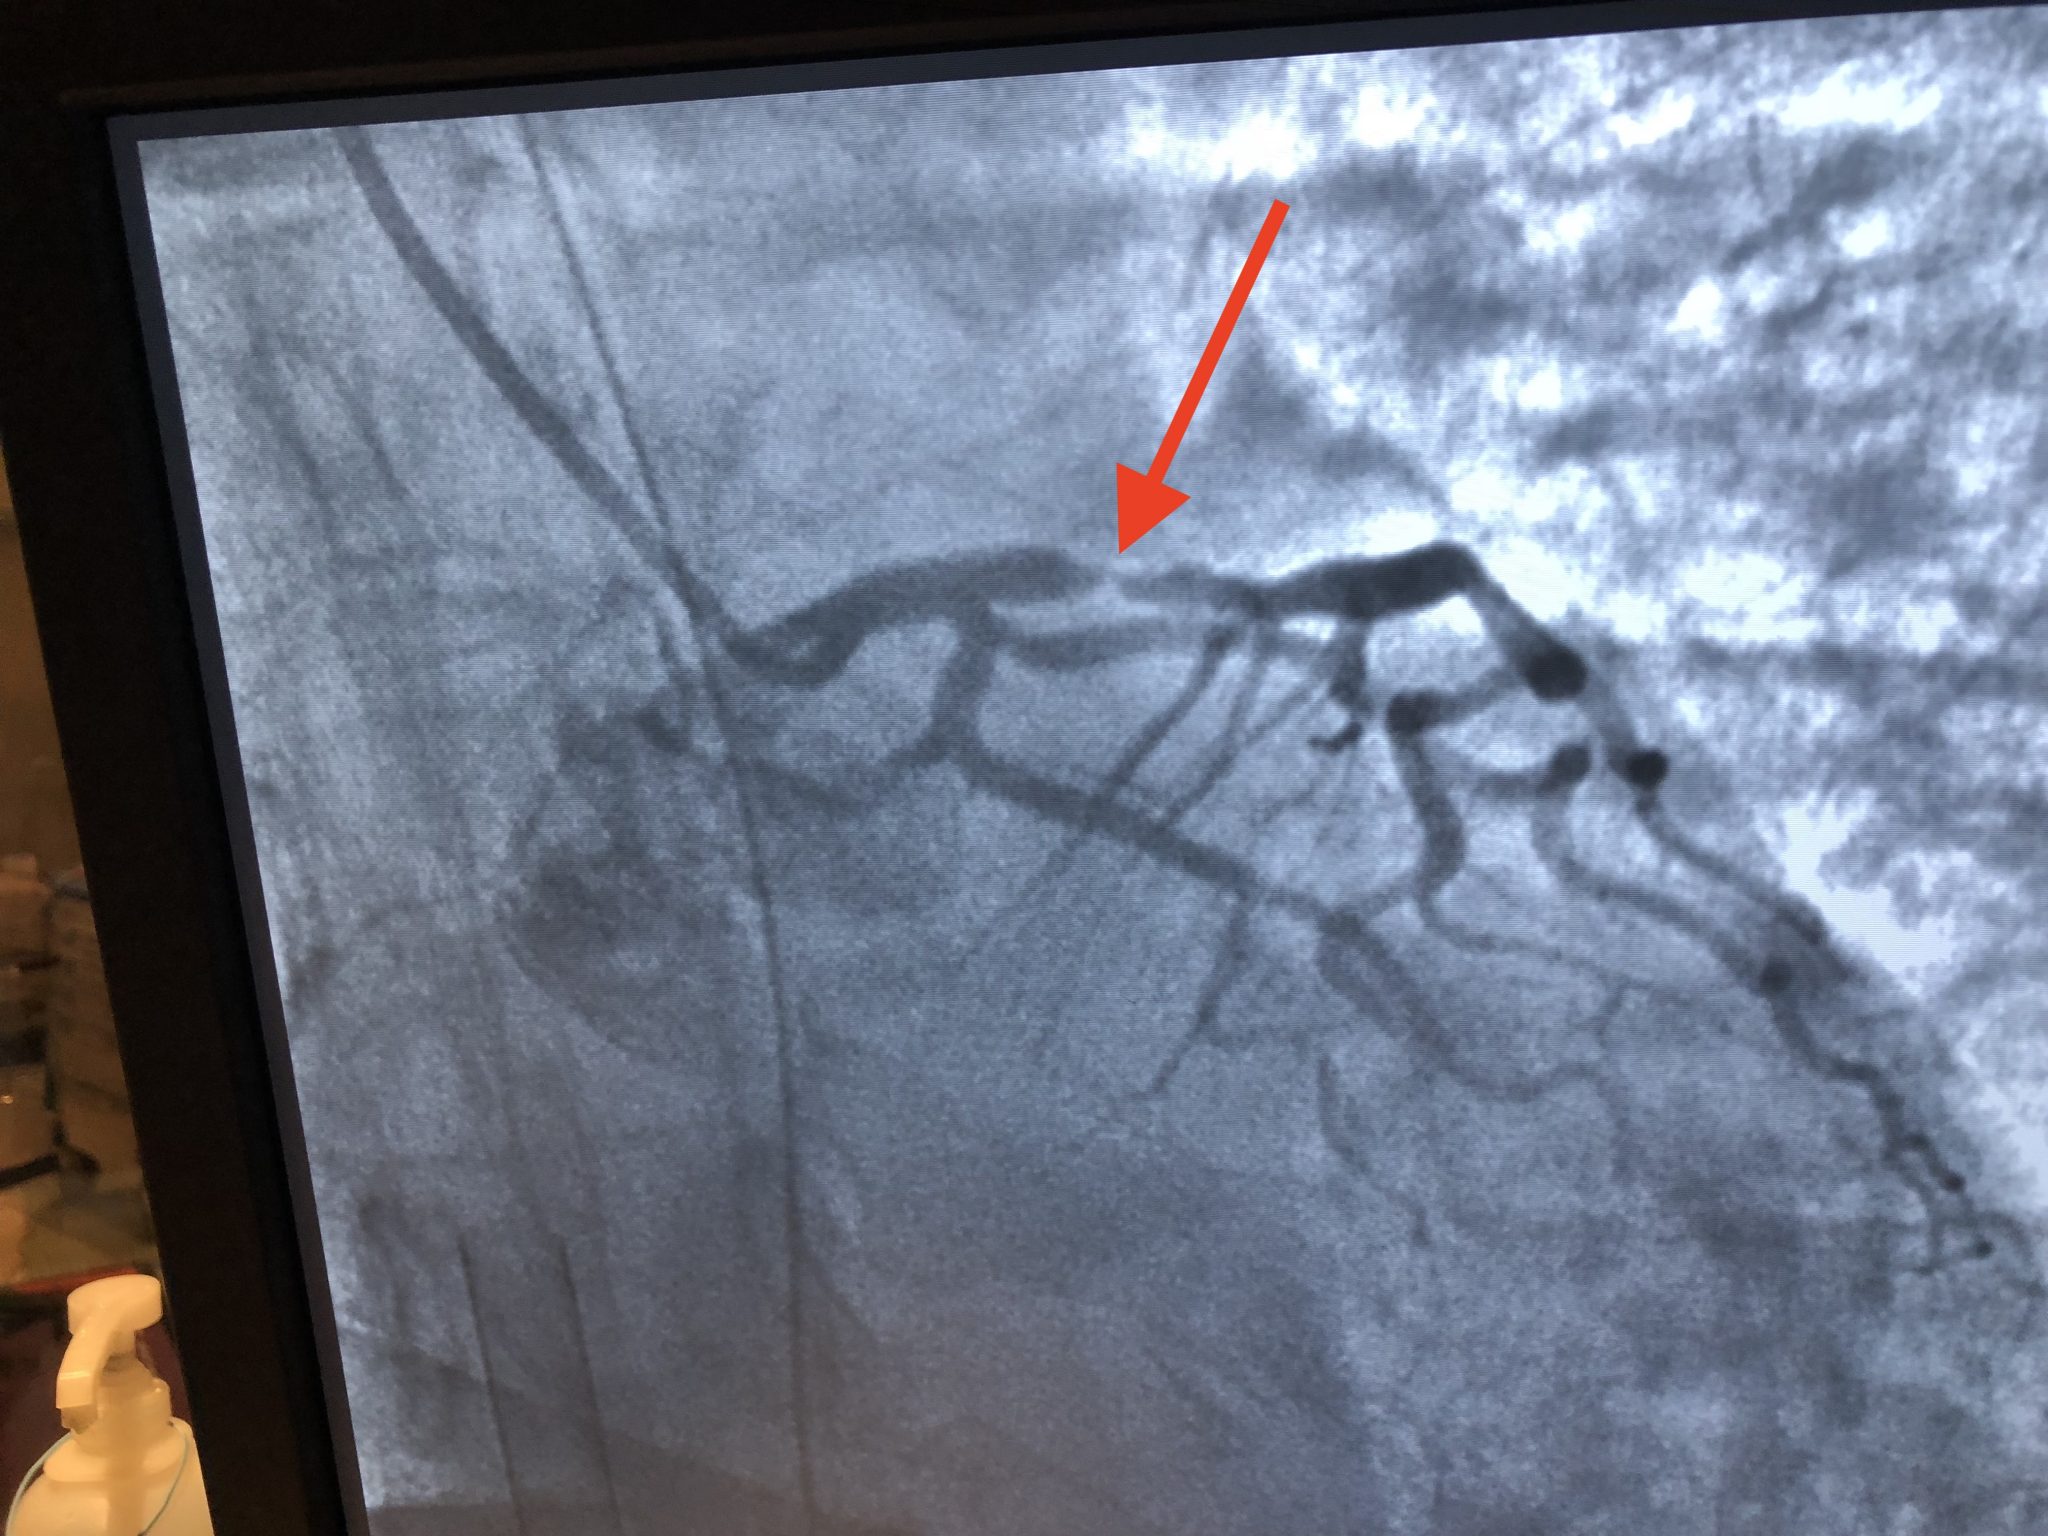

Our Emergency Physician-initiated ECMO (ED-ECMO) protocol was initiated using the ‘3 stages of ECMO.' Diane was ‘on pump' in 32 minutes, taken to the cath lab, and had her 95% LAD lesion stented by Interventional Cardiologist Arvin Narula.

Diane's Widowmaker